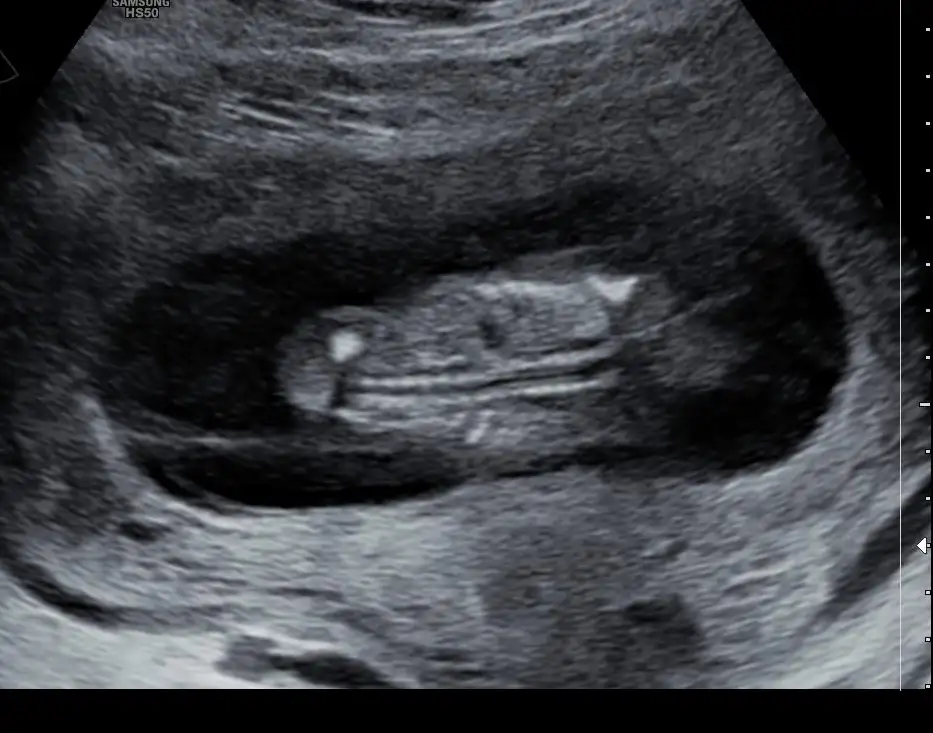

Kızlar merhaba, banada 11 artı 5 te yüzde 80 kız dedi, ama netten bakıyorum daha dıyo üreme organı olusma aşamasında.. Aslında bana farketmez ama insan merak ediyor neden bu kadar erken soyledi ki şüphede kaldık.

Doktorların yanılma payı her zaman var ama daha cinsiyet tomurcukları yeni oluşuyor. 16 17 haftadan önce söylenenlerin tutmama durumu daha yüksek

Ben de 11+6’da oglum olacagini ogrenmistim, oglum oldu. Bakan doktor cok iyi bi doktordu. Yani doktoruna gore degise debilir degismeye debilir